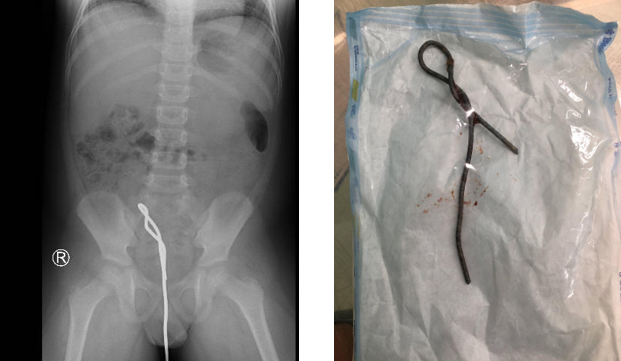

Vừa qua bệnh viện Nhi đồng Thành phố tiếp nhận một trẻ L. Q. H, 6 tuổi, nam, ngụ ở Cần Giuộc, Long An với thanh sắt dài khoảng 30cm phần bên ngoài, cắm vào hậu môn trẻ. Khai thác bệnh sử ghi nhận cách nhập viện khoảng 2 giờ, trong lúc đi vệ sinh trẻ lấy cây thông bồn cầu bằng kim loại nhét vào hậu môn, mục đích để lấy phân ra vì trẻ táo bón không đi ra được!?, sau đó trẻ không lấy ra được, than đau bụng nhiều, mẹ phát hiện nên đưa trẻ nhập bệnh viện Nhi đồng Thành phố. Tình trạng lúc nhập viện, trẻ lừ đừ, vẻ mặt hốt hoảng, than đau vùng bụng dưới, sinh hiệu ổn, bụng mềm, chướng, dị vật trong hậu môn là thanh sắt còn ở ngoài khoảng 30 cm, không chảy máu, chụp Xquang bụng không sửa soạn ghi nhận thanh sắt có uốn cong gắp đôi hình số 8 dài trên 10cm trong lòng hậu môn, trực tràng, đại tràng Sigma. Ngay lập tức các bác sĩ nội soi tiêu hóa phối hợp bác sĩ ngoại khoa, ê kíp gây mê hồi sức tiến hành gây mê trẻ, rút nhẹ thanh sắt ra nhưng vướng, nặng tay, nên được nội soi ổ bụng thám sát, ghi nhận có một mảng bầm kích thước 3x3cm ở thành bên phải đoạn cuối đại tràng Sigma, kiểm tra khộng thấy thủng ruột, kiểm tra thấy thanh kim loại nằm trong lòng đại tràng Sigma, đầu tận của thanh kim loại ghim vào thành sau hậu môn – trực tràng, nên phối hợp nội tiêu hóa dưới, gỡ đầu tận ra khỏi thành sau hậu môn, xoay và kéo nhẹ từ từ thanh kim loại ra khỏi hậu môn, khảo sát niêm mạc hậu môn và rìa xung quanh ghi nhận có trầy sướt niêm mạc – nơi đầu tận thanh sắt ghim vào, da rìa hậu môn rách 1,5cm ở vị trí 7 giờ, không thấy tổn thương cơ vòng hậu môn, nên được khâu da, bảo tồn niêm mạc. Trẻ được chuyển khoa Ngoại tổng hợp, tạm nhịn, nuôi ăn tĩnh mạch, theo dõi tình trạng thủng ruột, nhiễm trùng và điều trị thích hợp tiếp theo. May mắn thay sau 1 tuần theo dõi trẻ không có biều hiện biến chứng gì và có thể ăn uống trở lại đường miệng, tiêu phân vàng và được xuất viện tái khám theo hẹn.